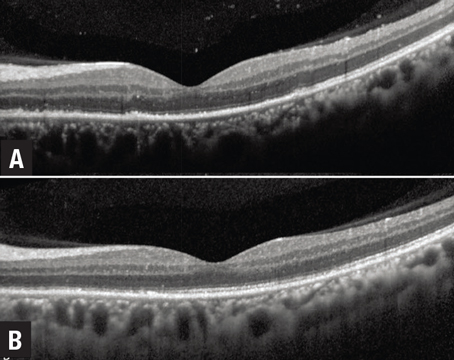

OCT biomarkers in uveitis: An update

A review of currently used findings that can help predict disease activity and functional response.